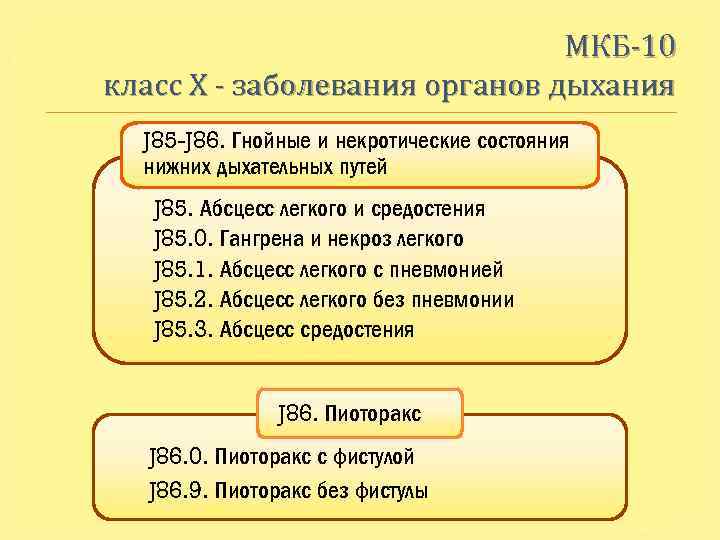

Код мкб 10 атерома головы

Код мкб 10 атерома головы 109 фото